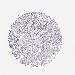

MELANOMA - Protein expressioni

A mouse-over function shows sample information and annotation data. Click on an image to view it in a full screen mode. Samples can be filtered based on level of antibody staining by selecting one or several of the following categories: high, medium, low and not detected. The assay and annotation is described here.

Note that samples used for immunohistochemistry by the Human Protein Atlas do not correspond to samples in the TCGA dataset.

Antibody stainingi

Antibody staining in the annotated cell types in the current human tissue is reported as not detected, low, medium, or high, based on conventional immunohistochemistry profiling in selected tissues. This score is based on the combination of the staining intensity and fraction of stained cells.

Each image is clickable and will lead to virtual microscopy that enables deeper exploration of all samples and also displays staining intensity scores, fraction scores and subcellular localization as well as patient and tissue information for each sample.

Antibody HPA032047

Antibody CAB002139

Staining

High

Medium

Low

Not detected

Intensity

Strong

Moderate

Weak

Negative

Quantity

>75%

75%-25%

<25%

None

Location

Nuclear

Cytoplasmic/membranous

Cytoplasmic/membranous,nuclear

Malignant melanoma, NOS

Malignant melanoma, Metastatic site